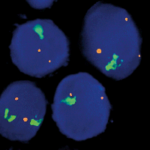

Quick Order Quick Order Name Email Address Company Address Catalog Number Quantity Message 14 + 5 = Submit Category Blocking Reagents Both Counterstain Country International US Detection Kit Detection Kit Detection kit 1-Step Polymer Kit Detection Kits - IHC 1-Step Polymer HRP Kits IHC AP Detection Kit IHC HRP Detection Kit IHC Mouse on Mouse 1-step Poly HRP kit New & Improved 1-Step Polymer HRP Kit IHC New & Improved Polymer HRP Kits IHC Polymer HRP Kits IHC Rapid Polymer HRP Kits IHC Double Staining eFISH Detection Kits ISH-Detection Kits Multiplex Detection Kits New & Improved Detection Kits Polymer HRP Kits IHC eFISH Enzymes for Tissue Processing Enzymes for Tissue Processing i6000 and Manual Instruments ISH Probes ISH-Detection Systems Links / Labels items-Manual Microscope Microchamber Slides & Coverslips for Xmatrx Microscope Slides & Accesories for i6000 and Manual Microscope Slides & Accessories Microscope Slides & Accessories miRNA Probes Primary Antibodies A Antibody Cocktail B C D E F G H I J K L M N O P R S T U V W Y Z Reagents Antigen Retrieval Solutions Blocking Reagents Blocking Reagents Buffers and Diluents Buffers eFSH Buffers ISH Buffers Counter Stains Detection Kit Dewaxing & Rehydration Reagents Diagnostic Antigen Retrieval Solutions eFISH Antigen Retrieval Solutions ISH Blocking Reagents ISH Enzymes Mounting Media eFISH Mount Media Nucleic Acid Retrieval Substrates & Chromogens ISH DAB replacements Slide Labels Vials Immunohistochemistry In situ Hybridization eFISH eFISH Probes eFISH Visualization Kits eFISH Visualization Kit Cyto eFISH Visualization Kit Histo Visualization Kit Ancillaries & Consumables Consumable Kits IHC Consumable Kits ISH Consumable Kits Counterstain and Mounting Media Counterstain Mounting PAP Pen Pipette Tips Reagent Vials & Accessories Reagent Vials & Accessories for i6000TM Diagnostics Reagent Vials & Accessories for Open system Automation Reagent Vials & Accessories for Xmatrx Elite Reagnet vials and accessories-1 Automation Detection Systems miRNA ISH Multiplexing & Double Staining Filters Sort results Reset Apply eFISH ETV6 Dual Color Break Apart Probe Select 10 tests (RTU)20 tests (RTU) Buy here eFISH ETV6 Dual Color Break Apart Probe Select 10 tests (RTU)20 tests (RTU) Buy here eFISH ETV6/RUNX1 Dual Color Dual Fusion Probe Select 10 tests (RTU)20 tests (RTU) Buy here eFISH ETV6/RUNX1 Dual Color Dual Fusion Probe Select 10 tests (RTU)20 tests (RTU) Buy here eFISH EWSR1 Dual Color Break Apart Probe Select 10 tests (RTU)20 tests (RTU) Buy here eFISH EWSR1 Dual Color Break Apart Probe Select 10 tests (RTU)20 tests (RTU) Buy here eFISH FGFR1/CEN 8 Dual Color Probe Select 10 tests (RTU)20 tests (RTU) Buy here eFISH FGFR1/CEN 8 Dual Color Probe Select 10 tests (RTU)20 tests (RTU) Buy here eFISH FGFR2/CEN 10 Dual Color Probe Select 10 tests (RTU)20 tests (RTU) Buy here eFISH FGFR2/CEN 10 Dual Color Probe Select 10 tests (RTU)20 tests (RTU) Buy here ‹ 1 … 83 84 85 … 146 ›